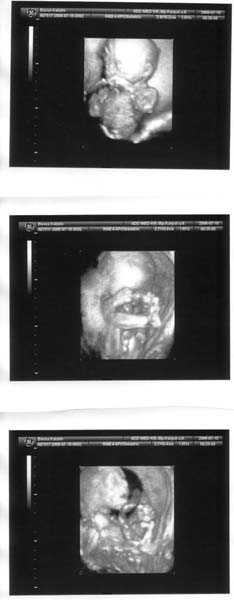

Megint suruek a napok 8) A hetvege egyik nagy esemenye hogy voltunk 3D UH-n.Kisteso jo kis meretes tanulsagat tette, hogy tenyleg kisfiu!!!!!! :lol: Teljesen beleszerelmesedtem, ahogy lattam a kis kerek pofijat,cui kezet,labat...annyira ereztem hogy O az enyem hogy nagyon imadom mar most!!!Tudom szentimentalisan hangzik,de ertitek Ti mire is gondolok :wink:

Kataa! Ezek az Uh-os felvételek NAGGYON CUKIK!!!!!! :lol: :lol:

Teljesen meghatódtam tőlük, annyira hihetetlen, hogy egy ilyen parányi kis emberke lakik a pocakodban. (a saját pocakjaimat is hasonló csodálattal és ámulattal figyeltem). Ez tényleg a legnagyobb boldogság a világon :lol: :lol:

Imádom ezeket a 3D-s képeket! Mint a kis madárfiókák :D